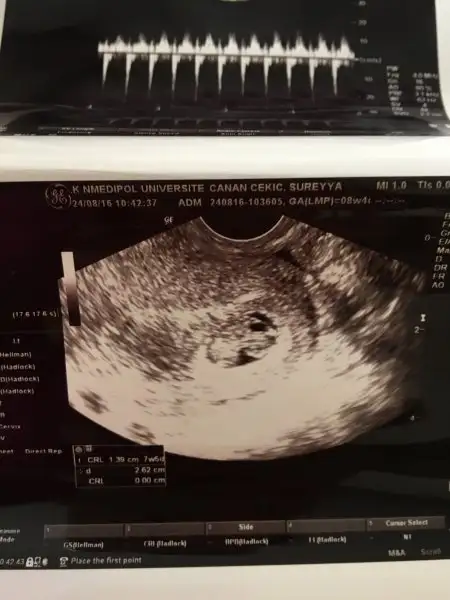

Hımm doktor bebek solda mi demişti öyleyse benim ki de sağda :) oy annesi yesin onu :)))öyle değildi benimki farklıydı :) ama eşim videomu cekmişti benim hastanede. kalp atışlarını duymak için. burdan videoyu size yollamak isteirm yollanabiliyorsa. benim sağımda kistim var, solumda bebek. monitorden bakınca kist solda gözüküyor yani tam tersi.

sana 7 ahftalıkken fotomu yolluyorum. bak kağıtta sağ yukarı tarafta. :) ama esasen solumda. kağıttaki soldaki de kocaman bir kist :)Hımm doktor bebek solda mi demişti öyleyse benim ki de sağda :) oy annesi yesin onu :)))

sana 7 ahftalıkken fotomu yolluyorum. bak kağıtta sağ yukarı tarafta. :) ama esasen solumda. kağıttaki soldaki de kocaman bir kist :)Eki Görüntüle 1876890

Kist neden bu kadar büyük bi zararı yok musana 7 ahftalıkken fotomu yolluyorum. bak kağıtta sağ yukarı tarafta. :) ama esasen solumda. kağıttaki soldaki de kocaman bir kist :)Eki Görüntüle 1876890